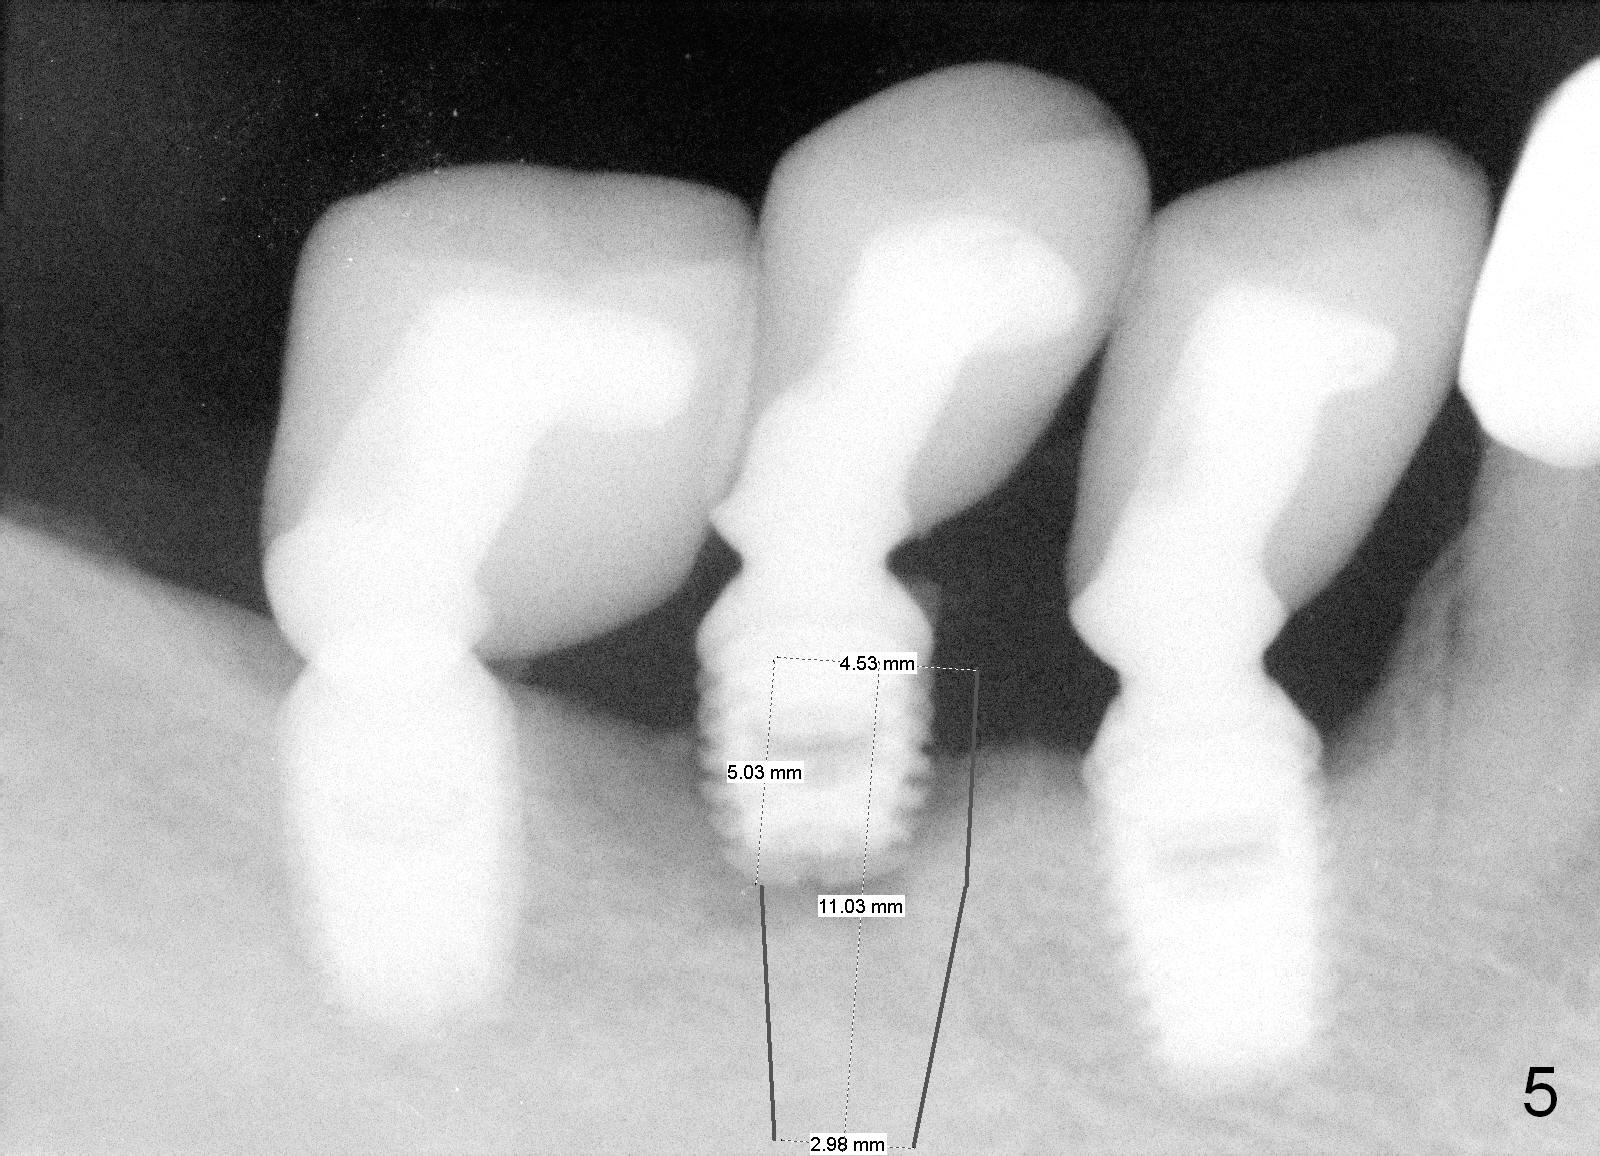

Immediate Re-placement of 2nd Premolar

A 48-year-old man had 3 implants placed at #28-30 nearly 10 years ago (Fig.1). The implant at #29 is 4.5x6 mm because of proximity to the Mental Foramen. Bone shows gradual resorption around the implant at #29 two and 5 years postop (Fig. 2,3 >). It became loose when he accidentally bit on a piece of bone (Fig.4). A 4.5x11 (Fig.4) or 14 (Fig.2) mm tissue-level implant will be placed after Metronidazole treatment. CT will be taken tomorrow before surgery to further confirm the bone height. Since the previous implant was placed distally, the new one should be placed more mesially.